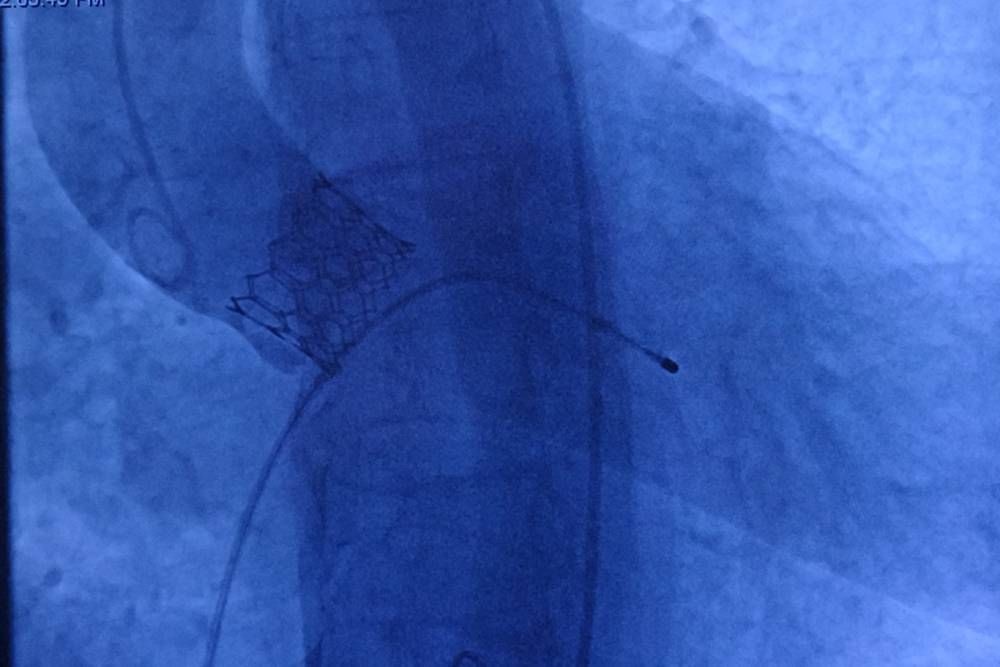

Nefes darlığı, göğüs ağrısı ve ciddi baş dönmesi şikayetleri ile Diyarbakır'dan Malatya Turgut Özal Tıp Merkezine başvuran, yapılan ekokardiyografisinde ileri derece aort darlığı tespit edilen 78 yaşındaki kadın hasta, Anjiyo yöntemiyle kalp kapağı başarılı bir şekilde değiştirilerek sağlığına kavuştu.

"78 Yaşındaki hastanın kalp kapakçığı TAVI yöntemiyle başarılı bir şekilde değiştirildi"

TAVI yöntemiyle tedavi edilen son hastalarından birinin 78 yaşında Diyarbakırlı bir kadın olduğunu belirten Pekdemir, hastanın yaşadığı şikayetleri şu sözlerle dile getirdi:

"Nefes darlığı, göğüs ağrısı ve son dönemde ciddi baş dönmeleri yaşayan hastamızın ekokardiyografisinde ileri derece aort darlığı tespit ettik. Açık ameliyatın yüksek riskli olması nedeniyle, kalp cerrahları ile yaptığımız değerlendirme sonucunda TAVI yöntemini uygulama kararı aldık. Anjiyo yöntemiyle kalp kapağını başarılı bir şekilde değiştirdik ve hastamız sağlığına kavuştu."